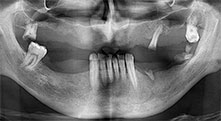

Würden Sie uns kurz beschreiben, wie Sie zum Beispiel beim Mobilisieren von Knochenblöcken für Transplantationen vorgehen?

Bratu: Wir bevorzugen Knochenentnahmen von der Linea obliqua externa des posterioren Unterkiefers, nicht aus der interforaminalen Region. Nach der Weichgewebsinzision verwenden wir die neuen Sägen, um den Umfang der Knochenentnahme zu definieren. Wir erledigen damit in fast 80 Prozent der Fälle auch die gesamte Präparation. Zusätzlich verwenden wir eventuell andere Piezo-Instrumente und zuletzt einen Meißel, um den Block zu mobilisieren. Das ist für uns eine sehr effektive Operationstechnik.